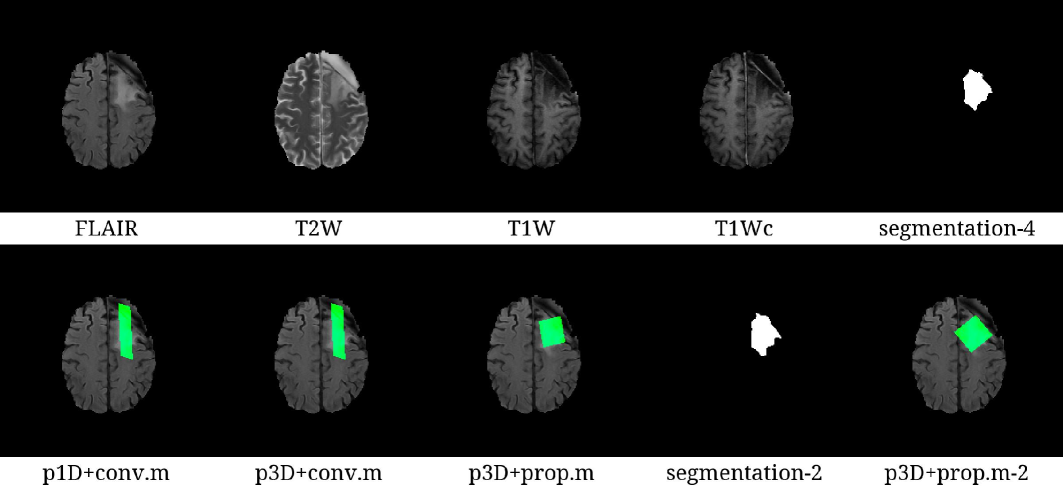

Figure 5: Representative images, tumor labels, and rectangular regions in the cases of searching 30×30×3030\times 30\times 30 mm3\text{mm}^{3} regions. The segmentation images represent estimated tumor regions. The rectangular regions were filled with green. As shown in the cases of the rectangular regions using the conventional metric (conv.m), the conventional metric preferred oblongs. The extracted shapes of the rectangular regions were similar in the cases of both 1-dimensional search (p1D) and 3-dimensional search (p3D). The shapes of the rectangular regions using the proposed metric (prop.m) were close to cubes since the proposed metric gave priority to cubes over oblongs. When the segmentation network with 2 inputs was used instead of that with 4 inputs, the results were slightly changed as shown in segmentation-2 and prop.m-2.

The processing times, volume of rectangular regions and tumor fractions are shown in Table 1. In the 1D cases, the proposed computation (7 seconds) was slower than the conventional computation (5-6 seconds). In the 3D cases, the proposed computation (8 seconds) was 100-500 times faster than the conventional computation (11-40 minutes). By comparing with the conv.m, use of the prop.m increased both volume of rectangular regions and tumor fractions without changing overall processing times. In the cases of searching 33753375 mm3\text{mm}^{3} rectangular regions, the processing times of the conventional computation were 5.26±0.215.26\pm 0.21 and 675.16±6.10675.16\pm 6.10 seconds for the 1D and 3D full search, respectively. Those of the proposed computation were 6.95±0.206.95\pm 0.20 and 8.19±0.128.19\pm 0.12 seconds for the 1D and 3D full search, respectively. In the cases of searching 2700027000 mm3\text{mm}^{3} rectangular regions, the processing times of the conventional computation were 5.56±0.215.56\pm 0.21 and 2410.6±13.92410.6\pm 13.9 seconds for the 1D and 3D full search, respectively. Those of the proposed computation were 7.00±0.177.00\pm 0.17 and 8.30±0.178.30\pm 0.17 seconds for the 1D and 3D full search, respectively. Representative images and their rectangular regions are shown in Fig. 5. As shown in the cases of the rectangular regions using the conventional metric (conv.m), the conventional metric preferred oblongs. In contrast, the shapes of the rectangular regions using the proposed metric were close to cubes since the proposed metric gave priority to cubes over oblongs.